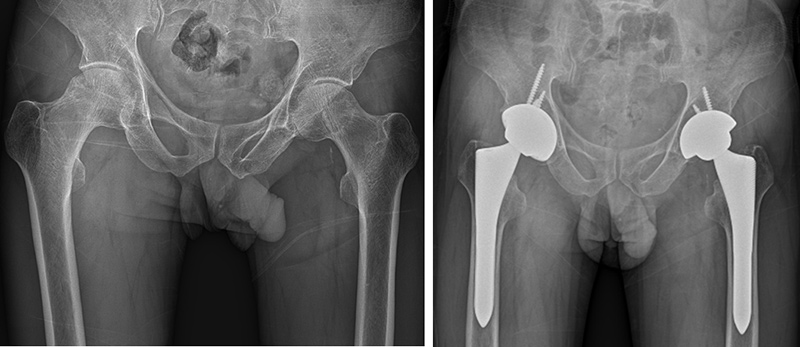

제 5 정형외과전문진료분야 고관절, 슬관절, 족관절, 인공관절 및 관절경, 골다공증

- 대한 정형외과학회 정회원

- 대한 고관절학회 정회원